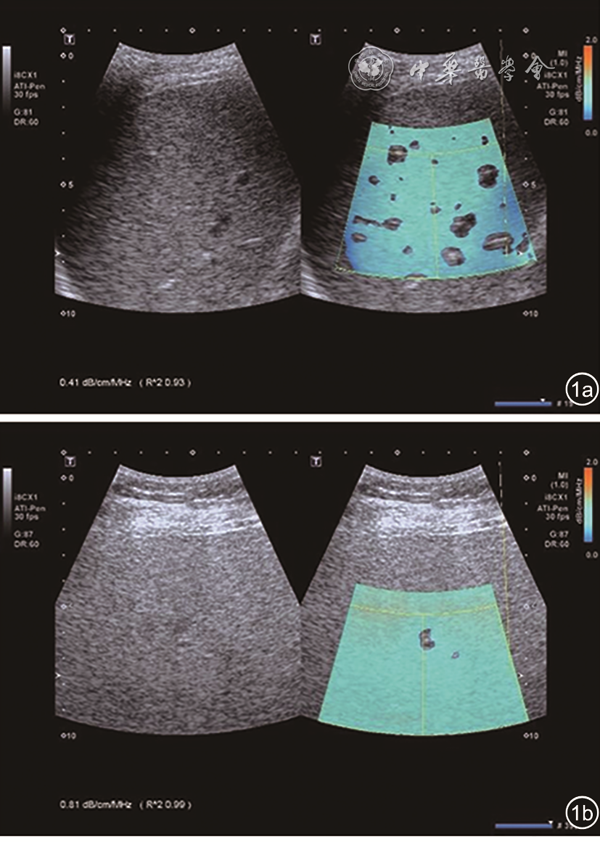

三、ATI技术评价肝脂肪变性的可行性分析